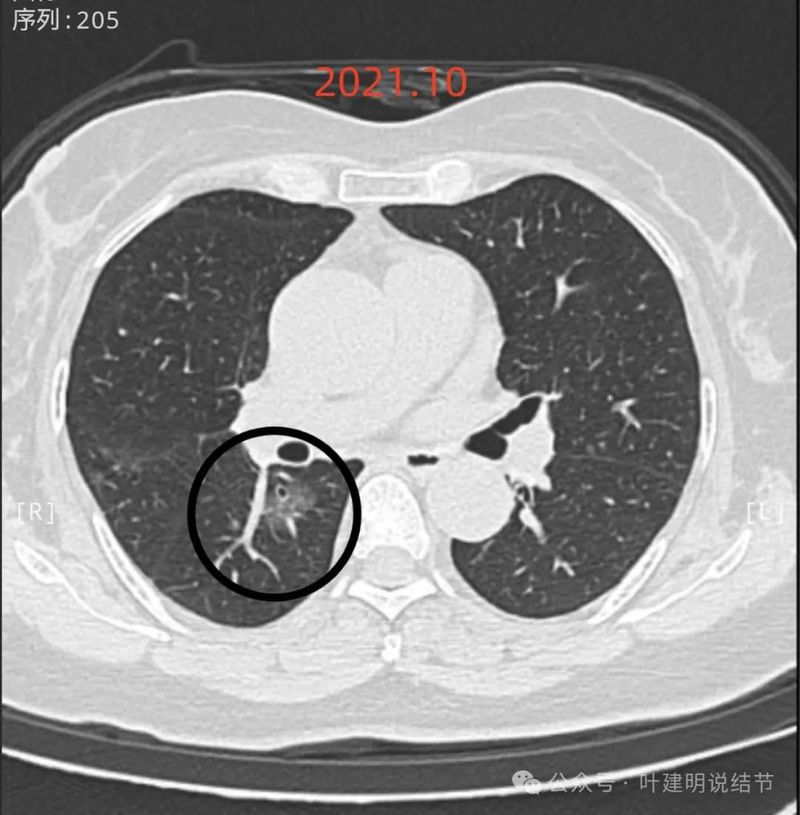

先看2021年10月时的影像:

右下叶背段混合密度结节,也有血管穿行,表面不光滑,轮廓与边界清楚,考虑微浸润性腺癌或浸润性腺癌贴壁为主型可能性较大。